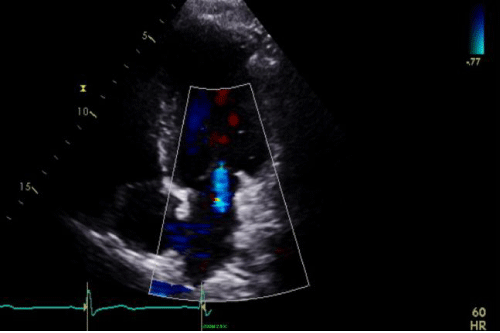

b) Repeat Echocardiogram: Mild increase in LV size and with LVEF = 40%. Mild mitral regurgitation (Figure 4).

Cine 2: Sinus rhythm (SR) with VR approximately 42 bpm. Transthoracic echocardiogram (TTE) demonstrating mild (central) MR with color flow